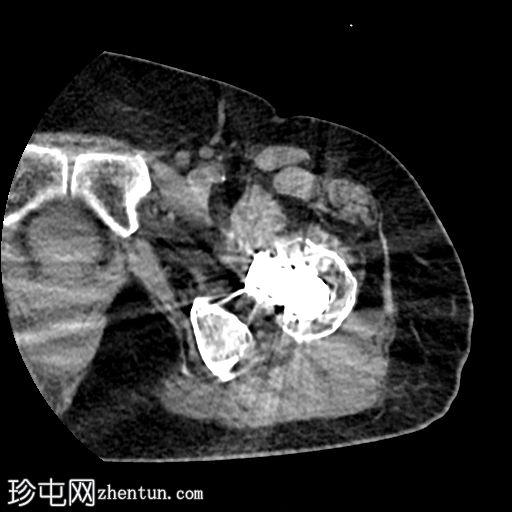

轴位片

平扫

左侧全髋关节置换术。大转子基底部可见轻微移位的假体周围骨折。

大转子滑囊积液,可见脂肪-液体平面。